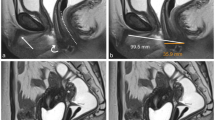

We measured AGD from anus to scrotum (AGDas) and to penis (AGDap) in 407 boys, and to posterior fourchette (AGDaf) and clitoris (AGDac) in 282 girls. Each measure was repeated three times at 3 and 18 months of age, and some children were, furthermore, examined by two different examiners. We assessed age-related changes and reproducibility of measurements.

AGD increased between the two examinations and correlated within the child. A large proportion of the observed variation in AGD was due to true differences between the children (AGDas: 62%, AGDap: 40%, AGDaf: 30%, AGDac: 21%), and measurement error due to between- and within-examiner variation was low.